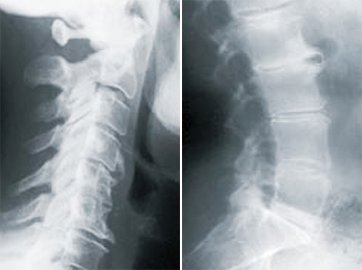

image

第1段階

• カーブの減少

• 軟部組織の緊張

• 軽度の可動域制限

• 神経組織の刺激